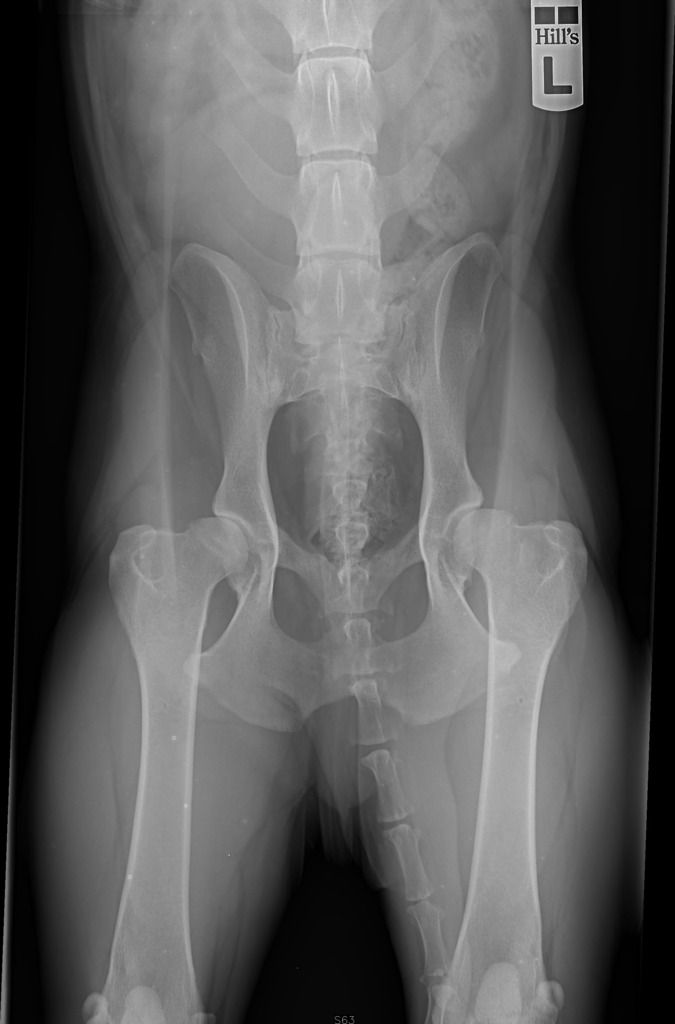

Maar er was een week geen training, en de week erop liep hij weer prima. Niets te zien. We dachten dat hij wellicht iets verrekt had, eerder, en dat hij daar wat last van had gehouden en dat het weekje extra rust voldoende was geweest. Daarna was er ook niets meer aan hem te merken, hij deed het allemaal enthousiast en hij ging zelfs béter springen. Tot hij ineens, een aantal weken geleden, minder enthousiast werd. Hij had er vooraf ontzettend veel zin in maar na één rondje wilde hij eigenlijk niet meer. Ik ben met hem naar een fysiotherapeut gegaan, en zij vond dat ik foto's moest laten maken omdat ze zijn heupen niet goed vond.

Die foto's hebben we gister laten maken en ik schrok me rot.

Hij loopt best goed trouwens, de dierenarts was heel verbaasd over de foto's met hoe hij binnen kwam lopen. We hebben wel pijnstillers mee gekregen, om te testen of het verschil maakt.